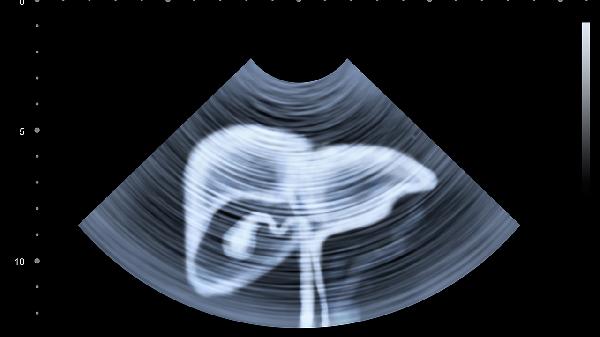

4、体检要看这些指标

除了常规B超,要特别关注ALT(谷丙转氨酶)、AST(谷草转氨酶)和γ-GT(谷氨酰转肽酶)这三个肝功能指标。建议每半年复查一次。